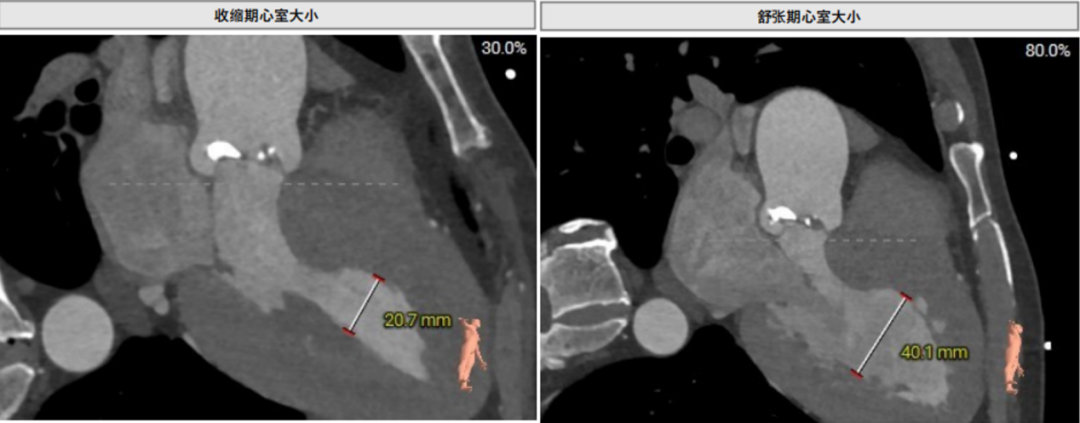

术前CT评估示

Type 0型纵裂式二叶瓣,瓣叶纤维增厚,重度钙化;主动脉瓣环周长折算直径31.0 mm,LVOT周长折算直径32.3 mm。

术前CT评估示

Type 1型二叶式主动脉瓣,L-R融合,瓣叶增厚,重度钙化,钙化主要分布于瓣叶上。瓣环周长89.3 mm,均径28.4 mm,LVOT周长89.7 mm,均径28.5 mm。瓣环处存在钙化,存在瓣周漏风险。